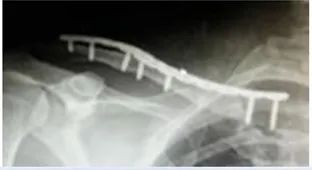

7、模型复位后,术前先进行钢板预弯塑性

8、术后X片